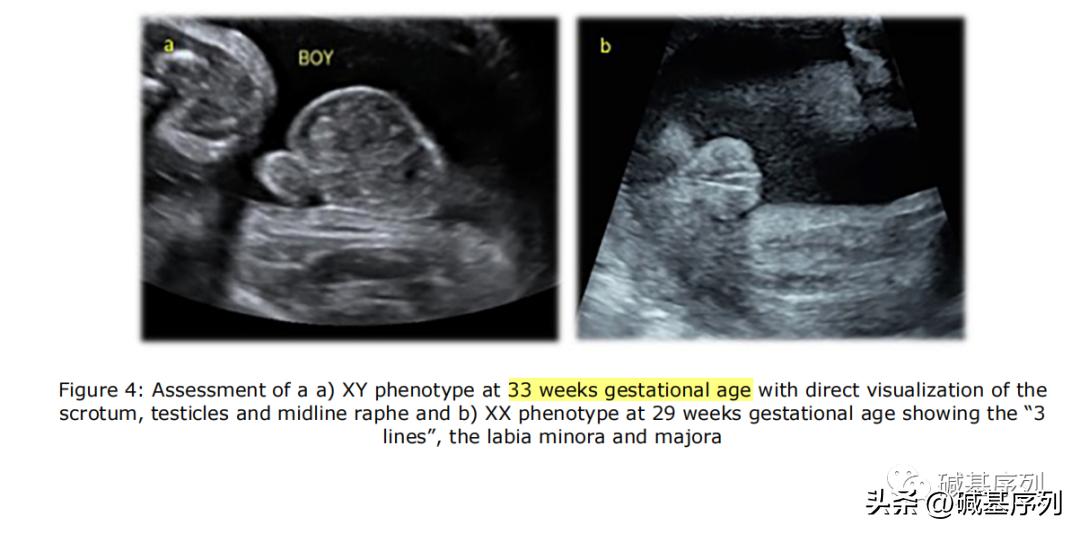

XX和XY基因型胎儿的超声表现

产前无创筛查(non-invasive prenatal testing, NIPT)发现性染色体异常。NIPT对性染色体非整倍体的阳性预测值(positive predictive value, PPV)约为32% ~ 57.6%。

在 Richardson等(2017) 研究中,NIPT提示的胎儿性别与孕期B超显示的胎儿性别之间不一致性的发生率为 1/1845 ,这个发生率已经 相当于或大于 一些常见的胎儿非整倍体或基因组疾病的发生率。例如,2q11.2缺失综合征(22q11.2 deletion syndrome, 22q11.2DS)是人类最常见的基因组疾病,活产儿发病率约 1/4 000~6 000。微缺失/微重复综合征发病率为1/200 000~1/4000,合并发病率近1/600。